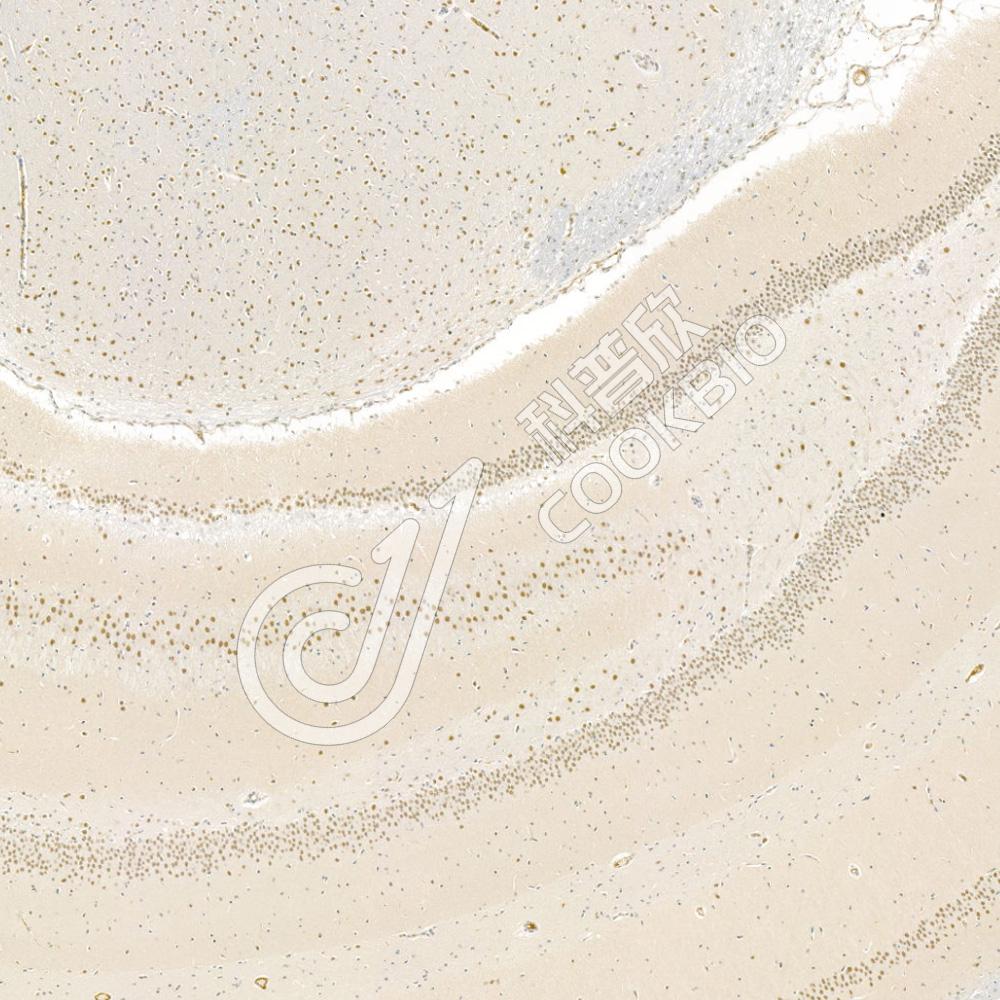

IHC检测HECTD1蛋白(货号 K1334182).

样品: 大鼠脑, 4%多聚甲醛 (货号KSG1101) 固定12-24小时.

抗原修复: 柠檬酸抗原修复液(干粉, pH 6.0) (KSG1201), 98℃, 20分钟.

—抗: 1: 1500稀释, 4℃ 孵育过夜.

二抗: S-vision免疫组化多聚二抗(山羊抗兔),即用型 (货号KB3906), 室温孵育20分钟.